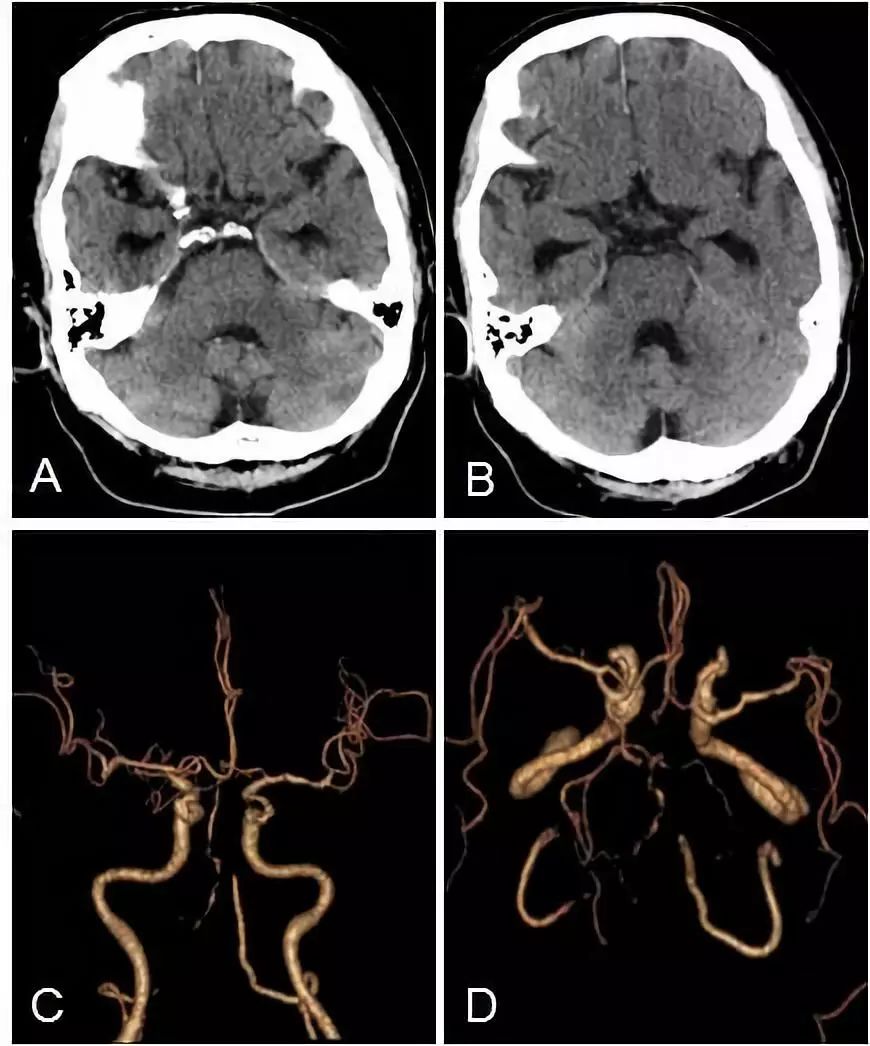

头颅CT+CTA:脑干及小脑半球多发梗死(图3A,B),双椎动脉V4段闭塞,基底动脉近段重度狭窄(图3C,D)。

图3

术后立即复查头CT未见出血(图6A,B)。

术后颅内动脉CTA:双椎动脉V4段闭塞;与术前CTA相比,右椎动脉V3闭塞段长度有增加(图6C,D)。

图6